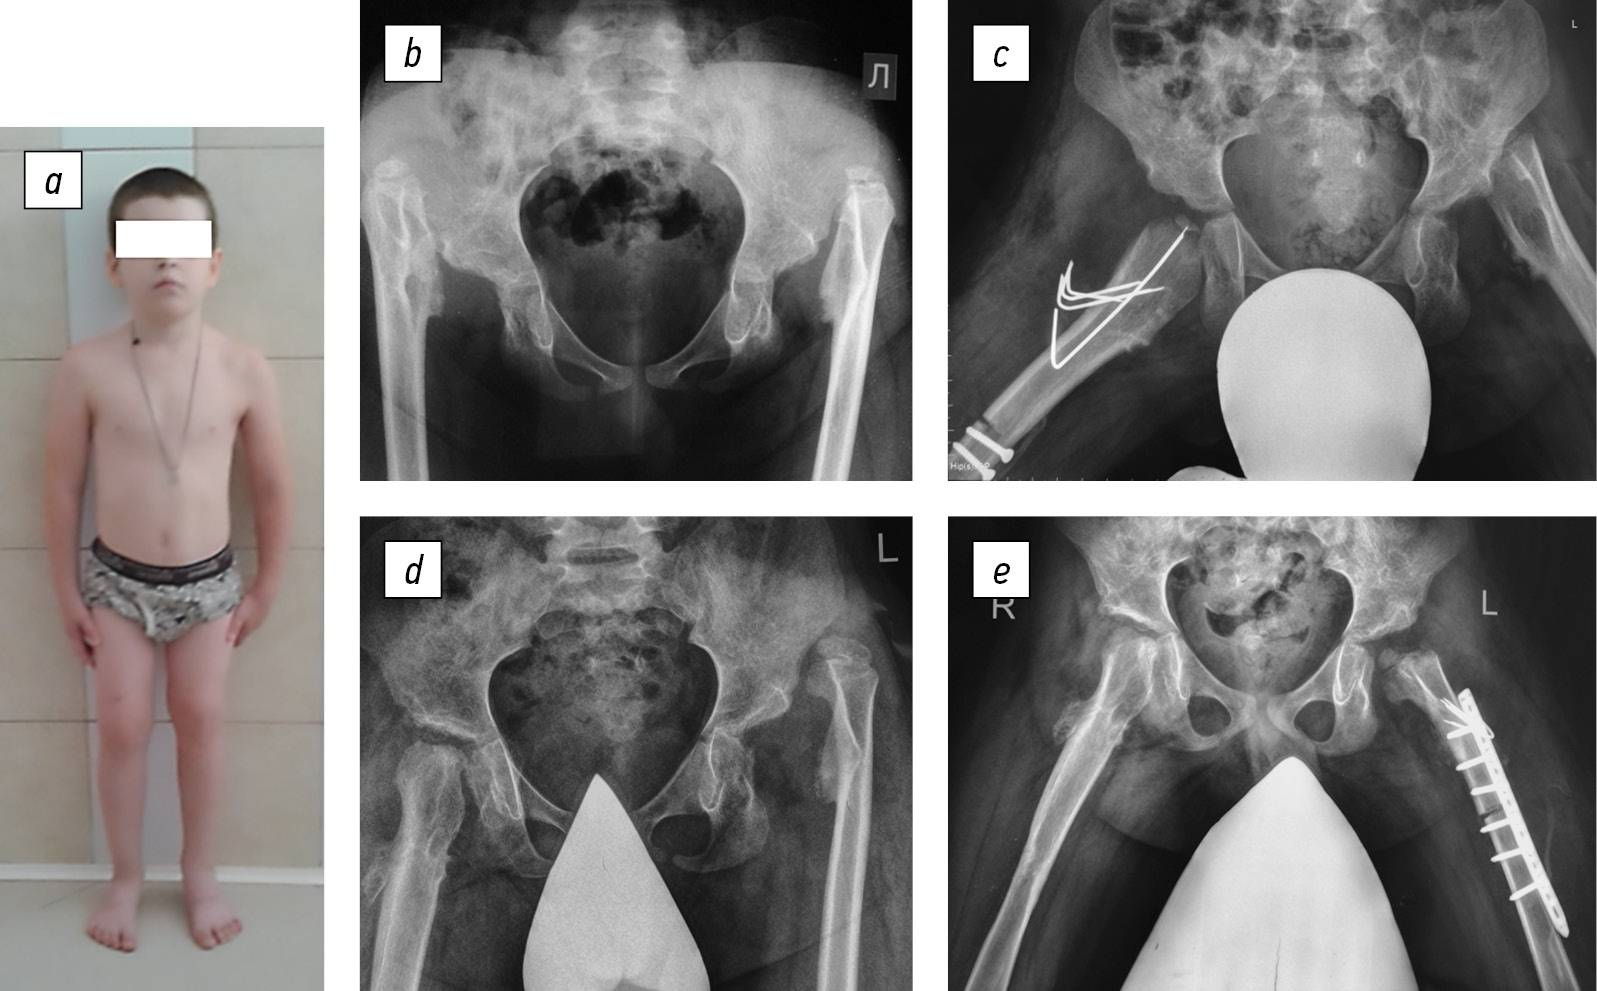

The child was admitted to the H.I. Turner National Medical Research Center for Сhildren’s Orthopedics and Trauma Surgery at the age of 6 years. He underwent surgical interventions to stabilize the hip joints, with an interval of 1.5 years. Therefore, in 2014 and 2015, hip arthroplasty was successively performed using demineralized bone and cartilage allografts. Concurrently, shortening detorsion osteotomies of the femoral bones were performed for joint decompression (Fig. 1).

Fig. 1. Appearance of the patient (a) and hip joint radiographs before (b) and at their surgical stabilization stages (c–e)